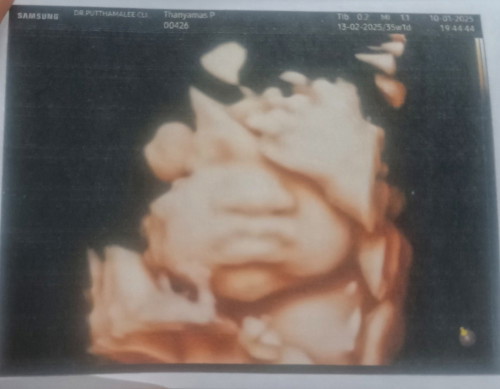

หลังคลอดกับตอนซาวด์หน้าตาลูกตรงปกมั้ยคะแม่ๆ อยากรู้ว่าลูกออกมาจะมีแก้มเหมือนตอนซาวด์มั้ย😅ซาวด์ตอน 35+1 นน. ลูก 2,652 กรัมค่ะ แก้มเยอะมาก